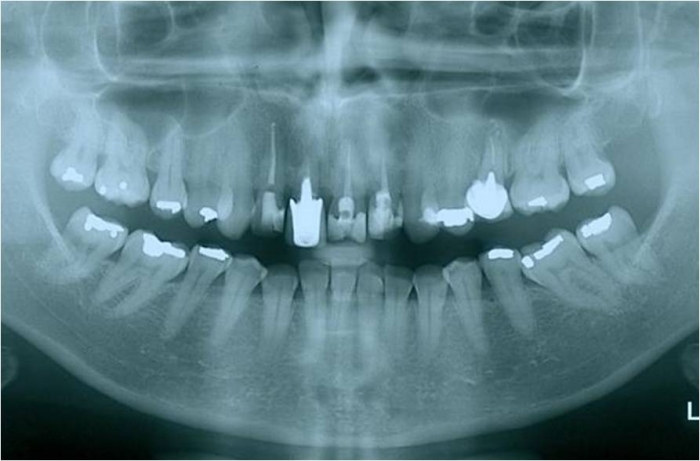

Imagens iniciais com dentes 11 e 25 comprometidos

Raio X inicial